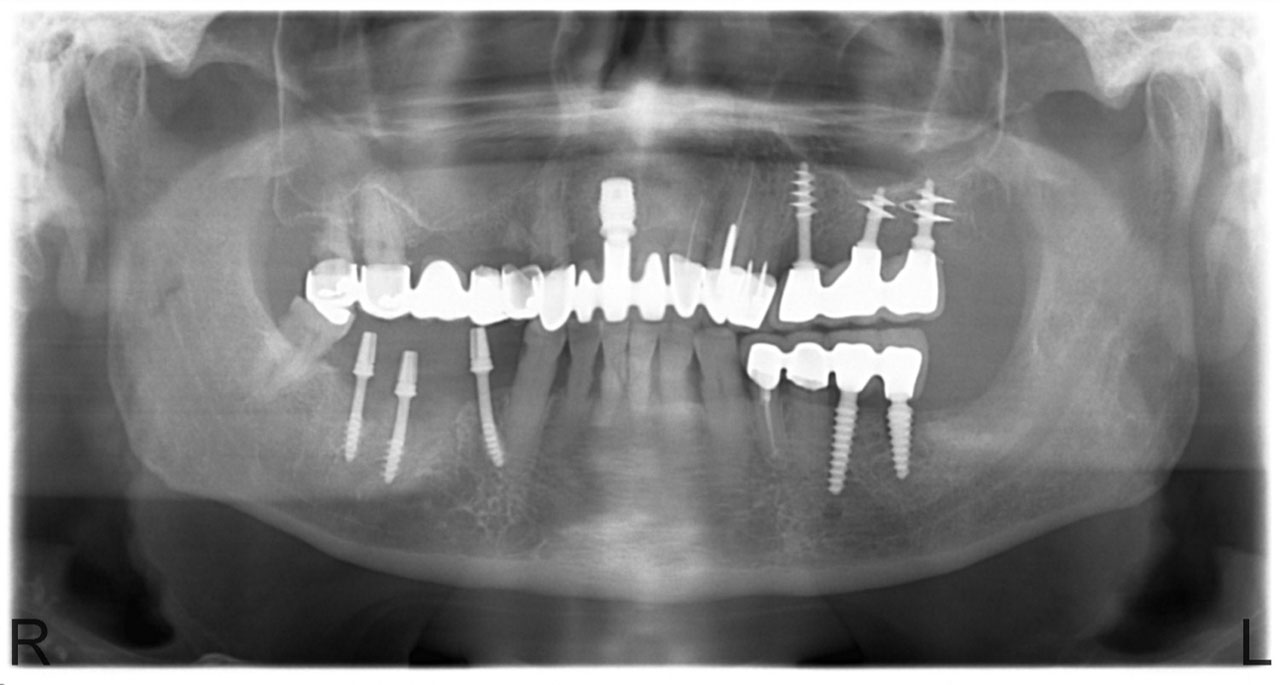

Implantáció előtt, gyulladt, törött fogak.

• esettanulmany-03

Imlantáció után,bal oldalon már a végleges hidakkal, jobb oldalon még csak az implantátumok.

• esettanulmany-04

Impantáció előtt, súlyos fogágy pusztulás, gyulladás látható.

• esettanulmany-06

Impantátumok a végleges híddal.